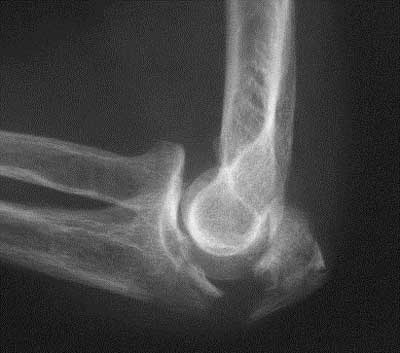

Luxation trans olécranienne

Dans ce cas, réduction au bloc est ostéosynthèse par plaque verrouillée.